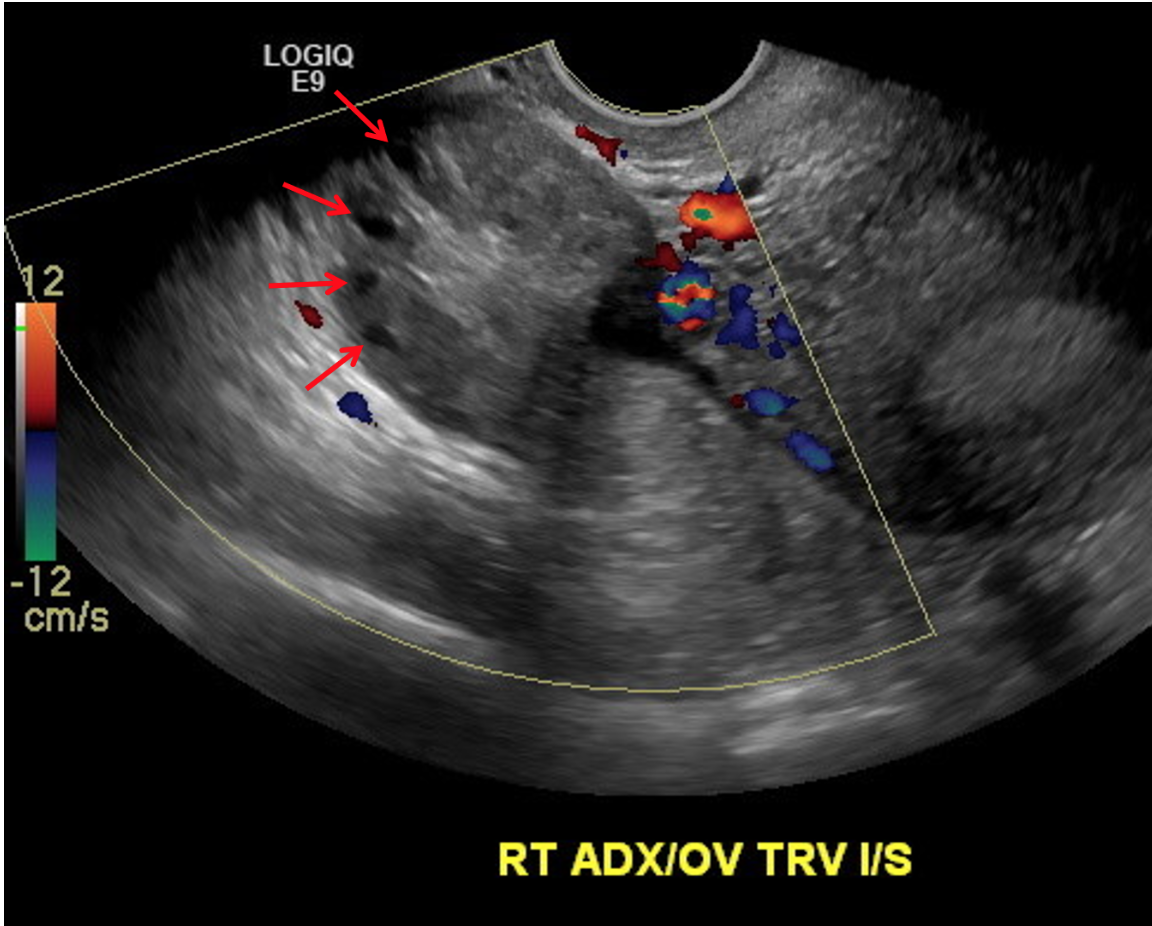

• Imaging findings

• Enlarged ovary (>4 cm)

• Lack of doppler flow (not required, can have torsion with flow!)

• Peripheralization of ovarian follicles (also seen in PCOS)

• Free pelvic fluid

Peripheralization of follicles and no internal doppler flow within the ovary